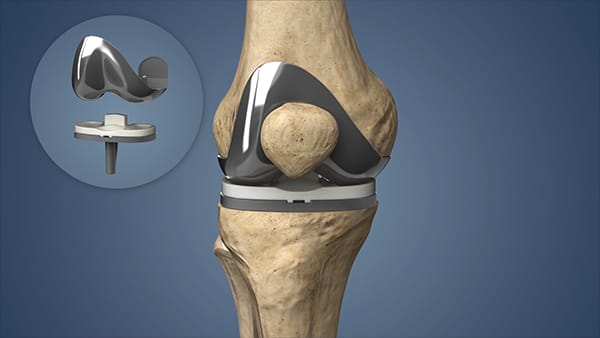

Total knee Replacement

Total Knee Replacement (TKR), also known as total knee arthroplasty, is a surgical procedure in which a damaged or worn-out knee joint is replaced with an artificial implant (prosthesis). This procedure is typically performed to relieve pain and restore function in patients with severe knee arthritis or joint damage.